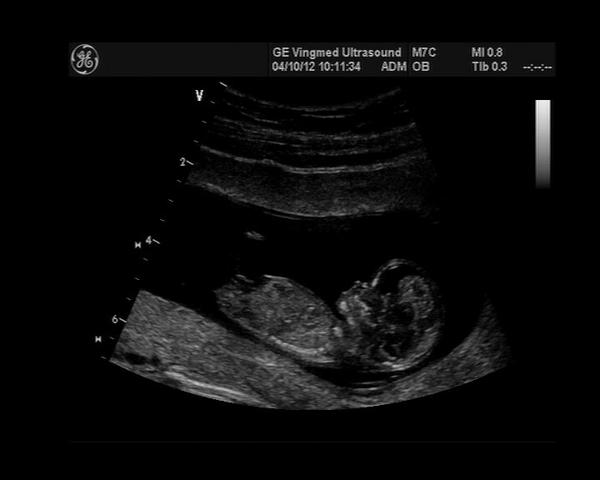

@briuska Ahoj Lucko, tak včera u pana primáře kontrola UZ, plodové vejce má 13,4mm což dle doktora odpovídá 5+1, ale včera jsem měla být 6+3. Jo a má srdíčko 🙂. Tak nevím jak to počítají, další KO až 14.10. Ještě ležím, dnes tedy už tak z poloviny, to flákání mě už nebaví. Ale snažím se šetřit jak nařídili klidový režim.

Na poslední fotce je ruka...a pět krásných prstíků 😀

@elliem jj, utz mi dělala taková mladičká doktorka, poprosila jsem jí o nahrání dat, za 100 Kč mi udělala CD s osmi fotkami. Přijela jsem domů a hned zapla PC a pak jsem se nemohla vynadívat, prohlížela jsem si je několikrát dokola 😀 ...a když jsem na monitoru viděla, jak se maličký hýbe, natahuje nohy, atd., konečně jsem měla najednou klid. Pak mi ještě dr. pustila srdíčko, to bylo jak když jede vlak 😀